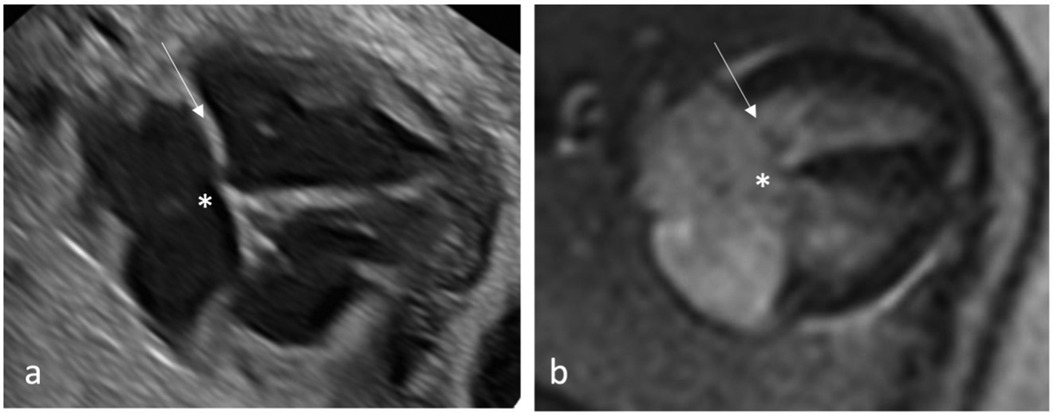

MR diagnostic quality of each anatomical structure/morphology assessed from the five axial views revealed highest scores for cardiac topography and situs and lowest scores for cardiac valves (Figures 2, 3).

Figure 2

Figure 3

Evaluation of the cardiac valves revealed to be difficult by cardiovascular MRI, indicated by lower diagnostic quality scores. However, it is also known from adult cardiovascular MRI that fetal echocardiography is superior to MRI in the evaluation of valve abnormalities (27). Difficulties in the detection of specific pathologies may be seen for both, fetal echocardiography and MRI, e.g., Ebstein's anomaly revealed limitations in the interpretability of both imaging modalities due to the enlarged right atrium. Detection of pathology in the 3V view, e.g., evaluation of the relationship of VCI, aorta and main pulmonary artery, with cardiovascular MRI also proved difficult (Table 1). One reason for the lower sensitivity of cardiovascular MRI in the detection of CHD in this study may be the limited experience of the analyzing radiologist with cardiac MRI in general and specifically with CHD. Therefore, detection rates could be higher with increasing routine and expertise in this complex field. However, quantitative analysis demonstrated that fetal cardiovascular MRI is comparable to fetal echocardiography as all diameters were similar for both methods.